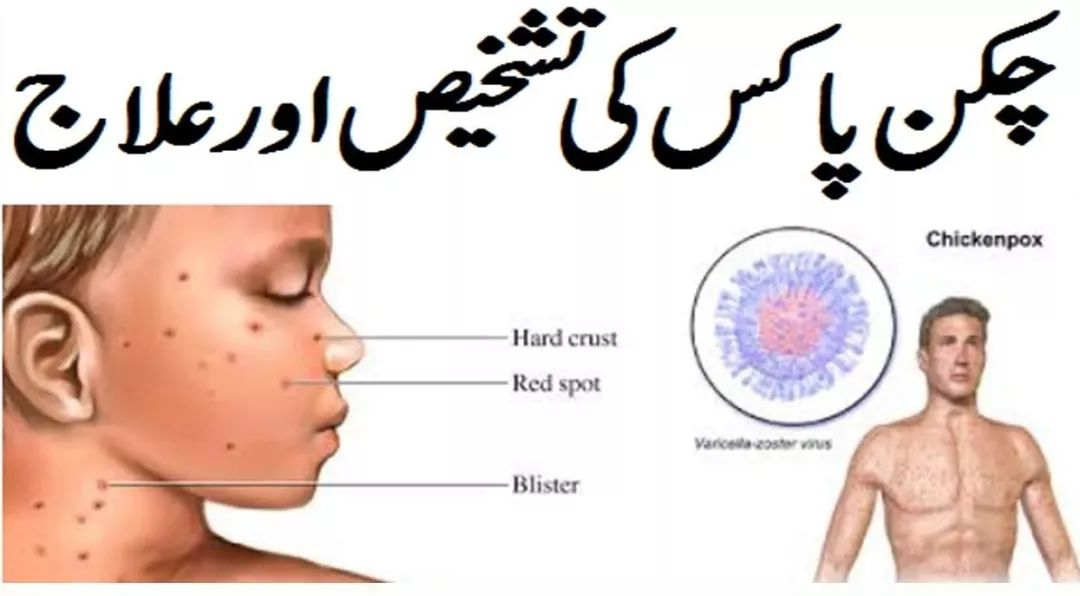

当VZV病毒首次攻破人体的免疫大军,感染人体之后,我们就长出了水痘。我们知道水痘常发生在婴幼儿和学龄前儿童身上,但请不要以为成年后就不会再长了。

与儿童很快就会被确诊为出水痘不同,成年人常常会将其误以为是感冒、发烧之类的,从而使病情更加严重。不出一个月,他们的头皮就开始疯狂长痘,冒水。脸,脖,甚至胸背上都出现像蚊子咬的大红点,并红肿起来成了一个个水痘、疱疹等。

通常,成年人得水痘的症状会更加严重一些。对他们来说,光是长痘毁容就已经很惨了,身上还又痒又痛。只要衣服稍微摩擦一下,都会痒得令人抓狂。可手又不能抓,因为一抓破就可能会再次感染留疤。